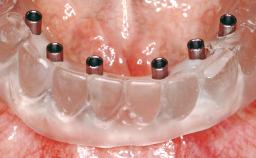

Immediate Loading of Two Implants in the Mandible and Final Restoration with a Bar-Supported RDP

Modality 2 interforaminal implants

Loading Protocol Immediate (bar only)